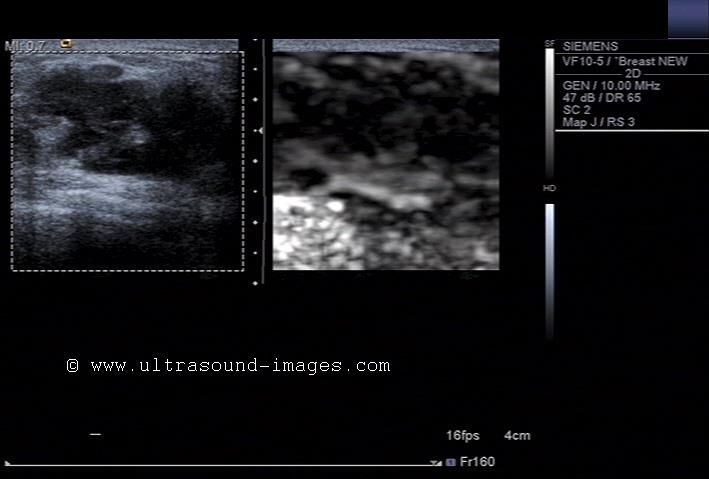

B-mode and 3D ultrasound image of carcinoma left breast